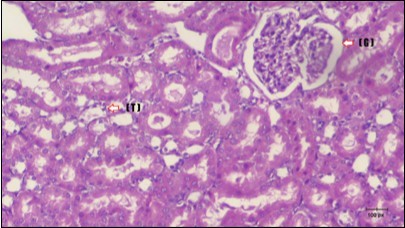

Kidney sections of diabetic rats showed an increase in mesangial cell and matrix of glomeruli with increase in glycogen deposition and hyalinization of arterioles with thickened basement membranes of proximal and distal convoluted tubules. These changes will lead to progressive reduction in the filtration surface of the glomeruli 35. Histological examination of the kidney of the control rats showed normal structure of renal glomerular. The proximal and distal tubules were lined with normal epithelium (Figure 13). The diabetic rats showed tubular casts, inflammatory cellular infiltration and glomerular atrophy (Figure 14). Kidney of rats in groups (3 and 4) showed some glomeruli return to be normal (G). Focal tubules casts (T) in Fenugreek group and some normal tubules in the Glimepiride group with no inflammatory cellular infiltrate in both groups (Figure 15 and Figure 16). However, kidney of rats in group (5) showed normal glomerular (G), normal tubules (T) with no tubular casts (Figure 17).

Figure 16.Photomicrogragh of kidney section of treated rat with Glimepiride showing improvement of Bowman,s capsules and partial improvement of glomerulir (arrow) and completely return of distal tubules and proximal tubules to the normal shape with wide urinary space. (H&E) (40X).